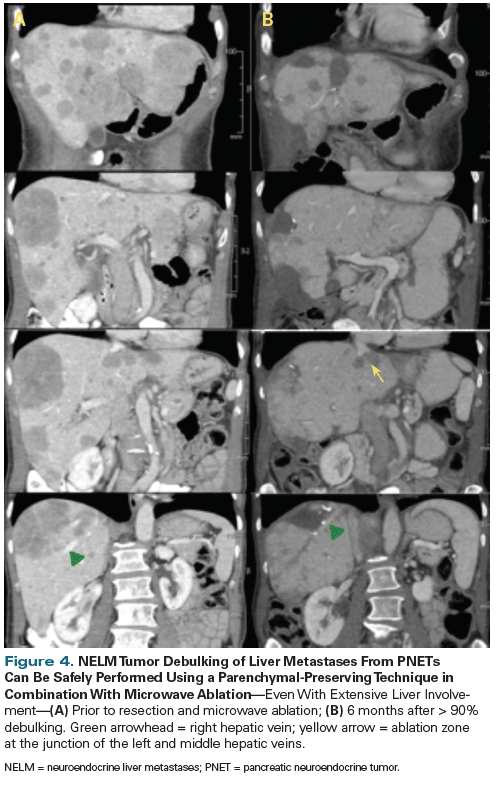

Figure 4. NELM Tumor Debulking of Liver Metastases From PNETs Can Be Safely Performed Using a Parenchymal-Preserving Technique in Combination With Microwave Ablation

Surgical rates have improved as surgical techniques have been refined. A shift toward parenchymal-preserving operations has led to a decrease in morbidity and mortality, with excellent oncologic outcomes even in patients with significant disease burden in the liver (Table 4). Parenchymal-preserving liver surgery is ideal for these well-encapsulated tumors, which are often amenable to enucleation (Figure 4). Nonanatomic resections in combination with ablation offer comparable oncologic results in small tumors.[54]

Many surgeons have advocated for a 70% threshold[43,44] for cytoreductive liver surgery (ie, proceeding to surgery if cytoreduction to at least 70% is deemed possible) instead of the traditional and more stringent 90% threshold,[55] maintaining that there is a survival benefit. Despite more advanced disease and a lower threshold for operating, contemporary surgical series report a 5-year overall survival (OS) rate of 74% to 80% with optimal surgical debulking and in combination with other therapies, in comparison with a historical 5-year OS rate of 40%.[43,56,57] Concomitant primary tumor resection is associated with a longer time to liver progression[58] and improvement in median survival up to 159 months.[58,59] With these excellent data, resection of neuroendocrine liver metastases, with or without primary tumor resection, should be considered in all patients with metastatic PNETs.